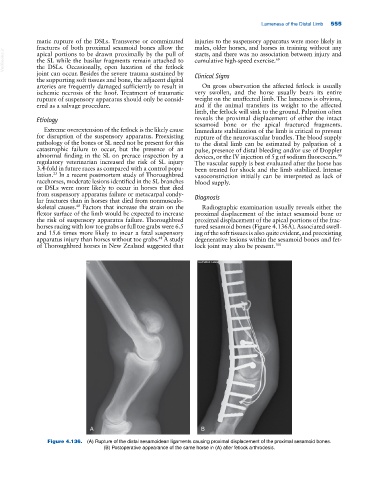

skeletal causes. Factors that increase the strain on the Radiographic examination usually reveals either the

flexor surface of the limb would be expected to increase proximal displacement of the intact sesamoid bone or

the risk of suspensory apparatus failure. Thoroughbred proximal displacement of the apical portions of the frac-

horses racing with low toe grabs or full toe grabs were 6.5 tured sesamoid bones (Figure 4.136A). Associated swell-

of Thoroughbred horses in New Zealand suggested that lock joint may also be present. 100

Figure 4.136. (A) Rupture of the distal sesamoidean ligaments causing proximal displacement of the proximal sesamoid bones.

(B) Postoperative appearance of the same horse in (A) after fetlock arthrodesis.